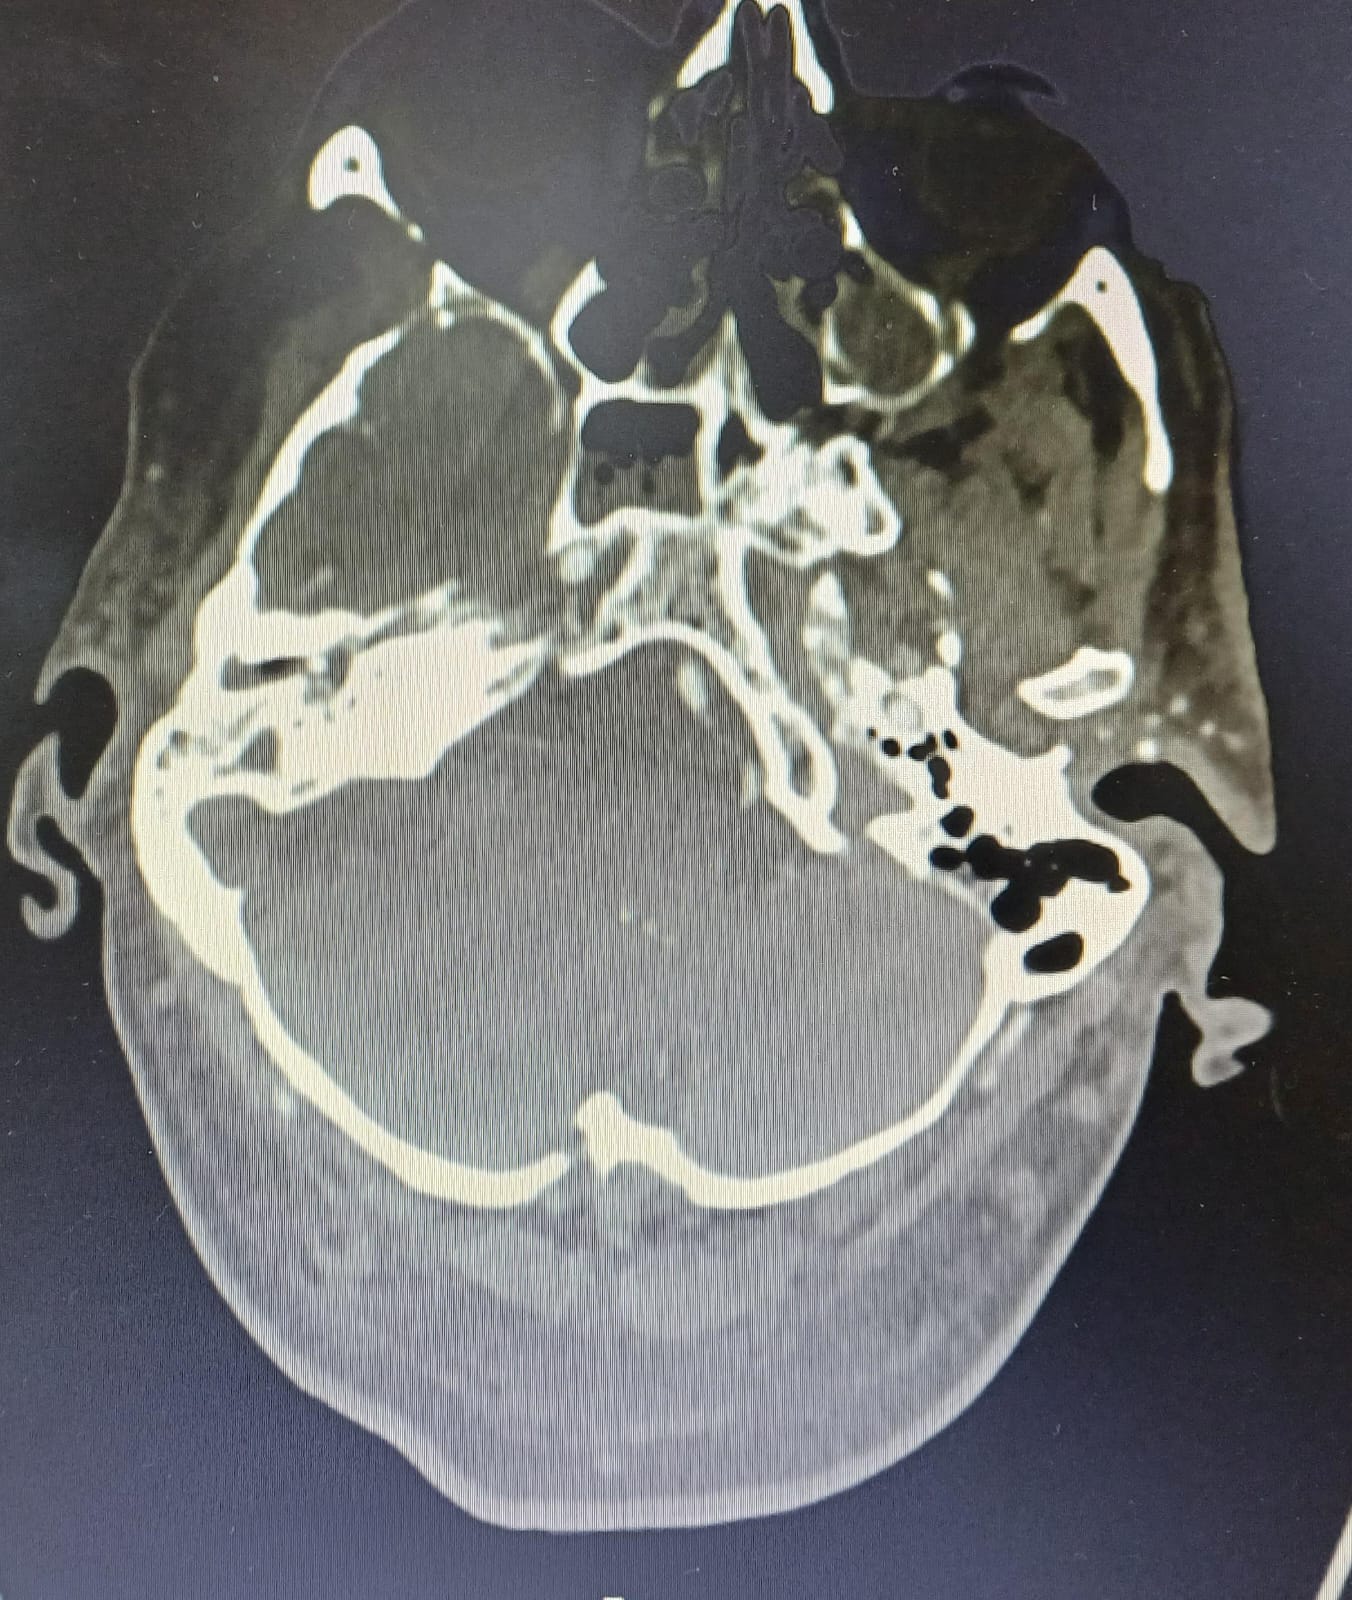

Meningoencefalitis otógena secundaria a OMA. Empiema subdural derecho. Tromboflebitis séptica en seno sigmoide y transverso distal derechos. Hemorragia subaracnoidea.

Manejo conservador conjunto Otorrinolaringología (ORL)y Neurología (NRL). Ante situación clínica se traslada a Unidad de Críticos y posteriormente ingreso en UMI para neurovigilancia con buena evolución. Seguimiento con TC y RNM cráneo y oído presentando ocupación de oído medio y celdillas mastoideas derechas, solución de continuidad en techo de mastoides con gas intracraneal. Empiema subdural en convexidad derecha 6 mm (previo 3 mm). Ante febrícula y leucocitosis mantenida se realiza nueva PL, con incremento de glucorraquia y sin gérmenes, se amplía antibioterapia a meropenem con buena evolución clínica posterior. Alta a planta de NRL con seguimiento por Unidad de Enfermedades Infecciosas.